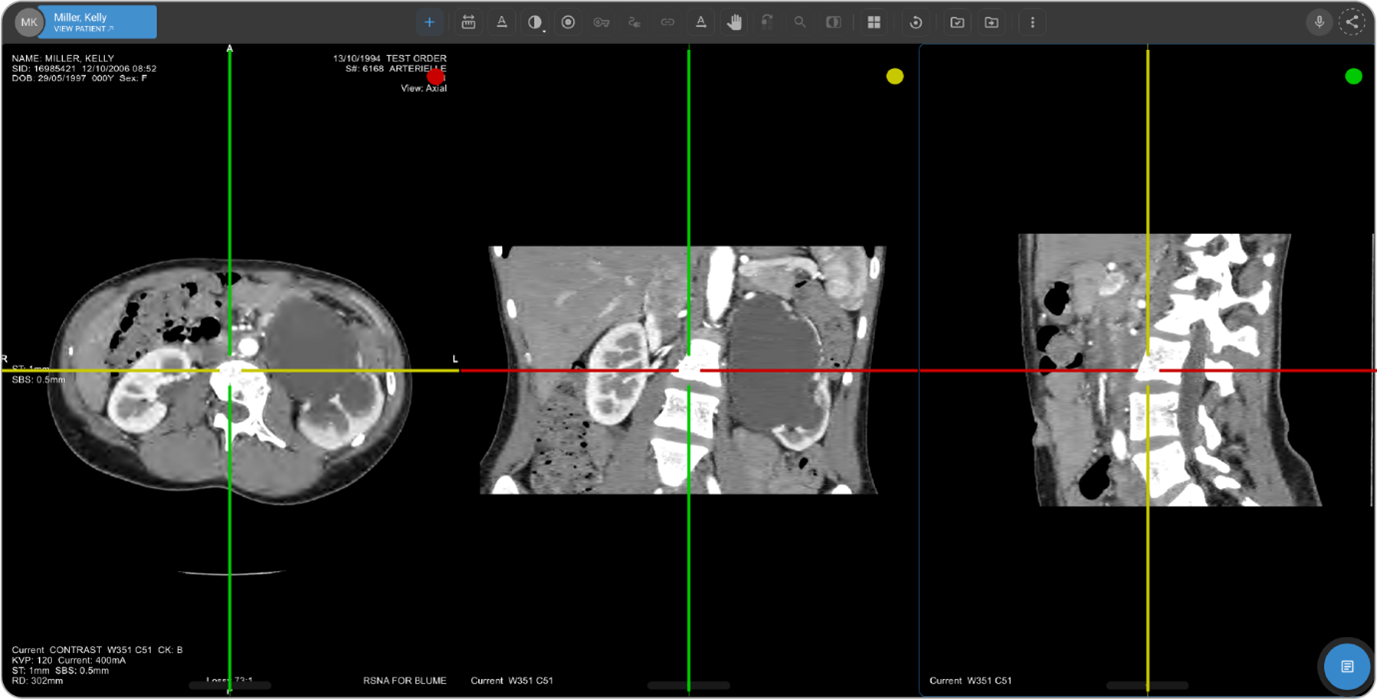

OmegaAI includes a feature known as Multi-Planar Reconstruction (MPR) M ode, essential for viewing complex imaging data in three orthogonal planes: axial, sagittal, and coronal.

Upon entering MPR Mode, the interface adjusts to display three viewports, each corresponding to one of the orthogonal planes:

Axial Viewport: Marked with a red dot at the top right corner.

Sagittal Viewport: Marked with a green dot.

Coronal Viewport: Marked with a yellow dot.

Each viewport will also display a full-screen crosshair with color-coded lines correlating with the view they represent:

Red Line: Axial

Green Line: Sagittal

Yellow Line: Coronal